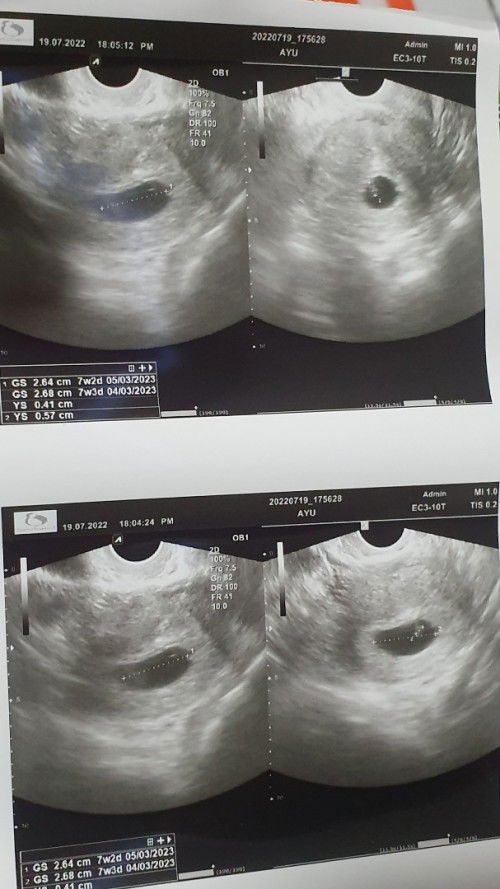

HPHT 22 MEI 2022. Gambar slide pertama, aku test pack H-3 sebelum haid Masih samar ,sampai slide ke 2 h-1 haid test pack pun masih samar. Akhirnya coba pakai clear blue emang the best deh langsung ketauan berapa week nya hihihi. Ternyata beneran positif. . Gambar slide 3, sabtu 25 juni 2022 akhirnya aku mutusin buat usg trans V di halomed.co.id (https://instagram.com/halomed.co.id?igshid=YmMyMTA2M2Y= ) lokasi kimia farma kebayoran lama (dokter nya enakk banget, cepet juga pelayanan nya ga sampe 10 menit nunggu udah dipanggil) harga nya pun masih kejankau 220rb. Dan kata dokter dari hasil usg ku yg masih sekitar 4week, memang masiu samar KANTUNG nya. Hihihi bunda bisa cek gmabar nya deh sambil zoom. Gapapa, yang penting aku udah mastiin ke dokter kalo kantungnya ada di rahim. Dan tidak ektopik (jujur takut banget ya bun, krna hamil pertama) . Terus dokter nanya, apakah aku ada keluhan? Alhamdulillah aku ga punya keluhan macem macem. Paling agak enek itu pun jarang banget muncul, dalam sehari pun blm tentu muncul, cuma laperan aja rasanya dan sering makan tiap bbrp jam dgn porsi dikit. Dan dokter cuma nyaranin aku minum vitamin buat kehamilan, aku info ke dokter aku udh minum prenatal dari natursplus gambar slide 4. Dan disini aku ga dikasih vitamin lain atau penguat kandungan. Mungkin krna aku ga ada keluhan apa apa dan usia skrg baru 24 tahun. . Dokter saranin aku buat balik lagi 4week kedepan, artinya di usia 8week deh kira kiraa. Katanya biar jelas kalo usia segitu. Oh iya, kemarin aku juga nanya prihal perlu gasih saya nambah susu hamil dok? Dokter bilang, vitamin yang aku konsumsi sudah sangat cukup buat nutrisi. Tapi rencana sih aku mau minum susu, krna aku tim suka kopi banget, jadi biar kealihin aja ganti kopi nya dengan susu hamil. Hehehe Sekian, semoga sharing ku membantu juga buat bunda yg hpl nya kurang lebih di bulan februari. #bantusharing #firstbaby